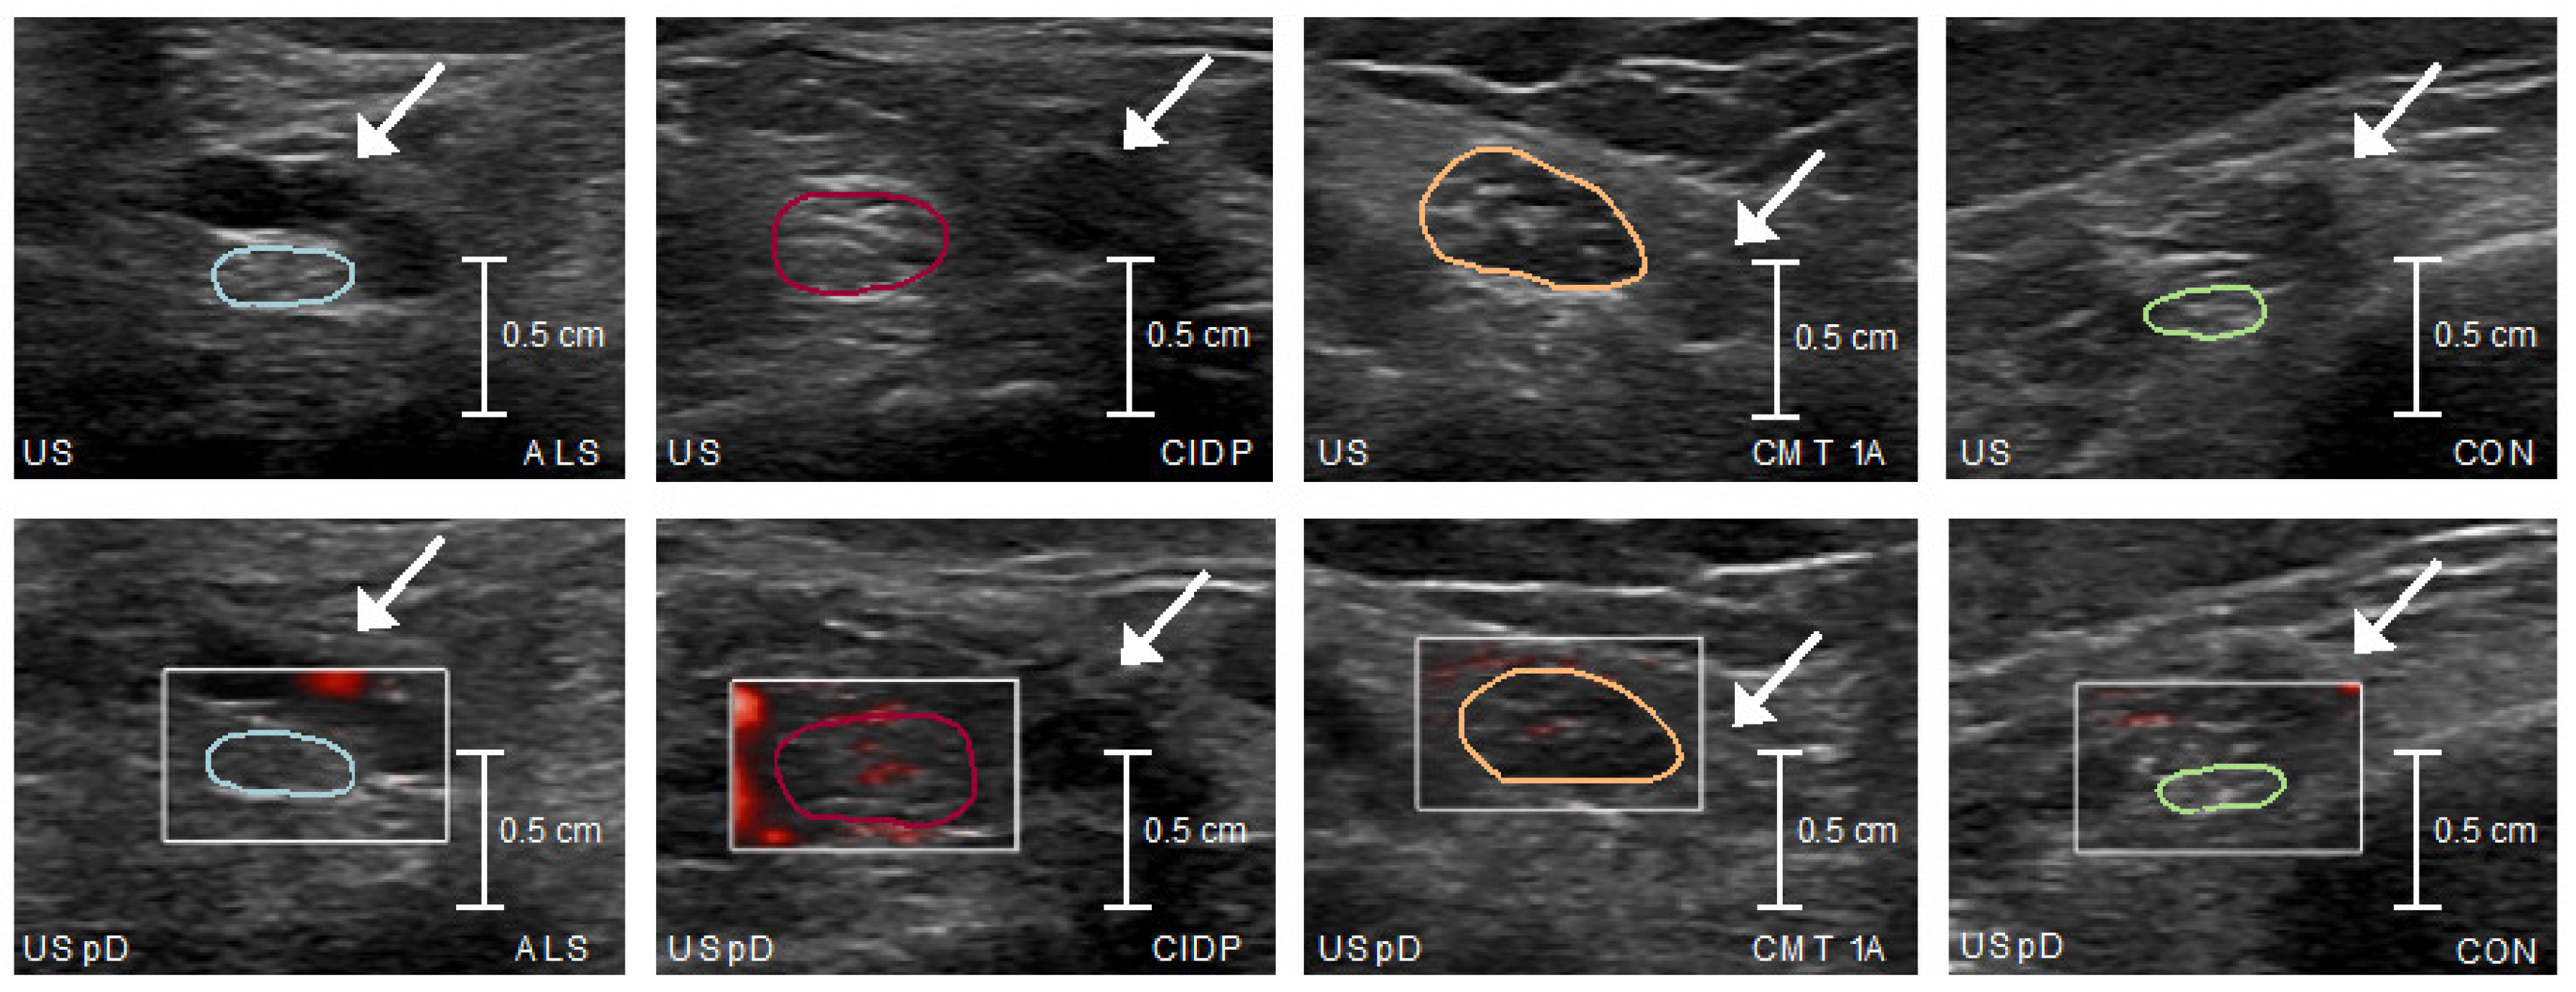

Comparing US measurements among subgroups, CSA was significantly larger in CMT and CIDP compared to ALS and controls, and microvascular blood flow was greatest in the CIDP cohort and higher than in CMT, ALS, and controls (Table 3 and Figure 1 and Figure 2).

Figure 2. Ultrasound and ultrasound power Doppler – tibial nerve. Color-coded tibial nerve cross-sectional areas; arrows indicate posterior tibial artery. US, Ultrasound; US pD, ultrasound power Doppler; ALS, Amyotrophic lateral sclerosis, CIDP, Chronic inflammatory demyelinating polyradiculopathy, CMT, Charcot-Marie-Tooth-disease; CON, Controls.